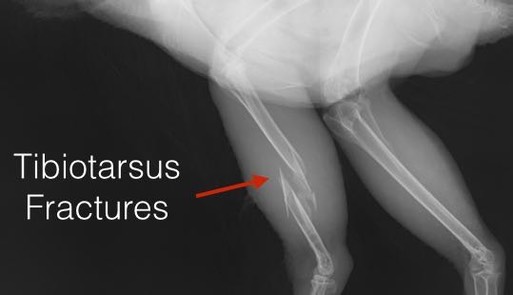

Fractures caused by a projectile tend to shatter the bone at the point of impact, as with this hawk. When cases such as this are admitted, the evidence is collected and presented to a veterinarian. If the vet concludes that the bird has likely been shot, the findings are reported to the authorities.

The outcome seemed poor for a surgical repair of the leg, so we opted for a conservative approach and applied a splint.